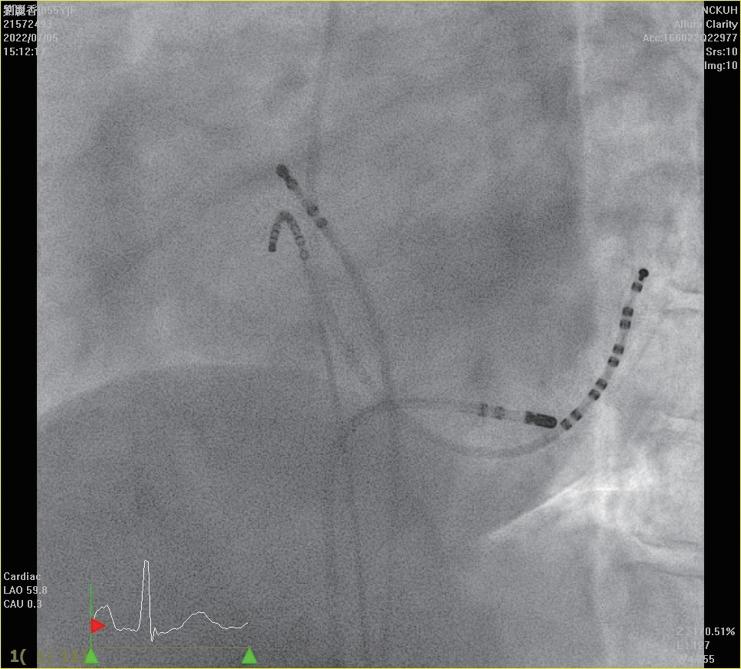

術製造皮下口袋(subcutaneous pocket)後,再以導線 經 Seldinger technique 建立靜脈的通道。接著,藉由 EnSite Precision 心臟定位系統,使用可控式 10 極導管 ( InquiryTM, steerable diagnostic catheter, SJM ), 自左鎖骨下靜脈、頭肱靜脈 , 上、下腔靜脈、右心房 以及右心室等立體結構,進行心血管系統之 3D 繪製 (圖二)。繪製時,會特別著重右心耳、右心尖與右 心室出口的結構與位置,以利後續置放進行。接著, 將心臟植入性電子儀器的導線連結於 EnSite 系統並成 像,在 3D 定位系統導引下,由先前繪製的構造中, 將導線尖端置於目標處(圖三),並進行相關參數測 試。選定適當位置進行導線固定時,由於目前系統無 法將主動固定的螺旋( screw)成像,因此無法確認螺 旋是否確實伸展。我們團隊於此步驟會藉由螢光檢查 檢視螺旋伸展的狀況、評估放置位置是否與預期相符 以及導線鬆弛程度( lead slack)是否適當。調整後, 完成心臟植入性電子儀器放置時,亦會再藉由螢光檢 查確認位置(圖四)。目前臺大單一中心經驗,藉由 3D 定位系統於 13 個病人中放置過 14 個儀器(3 個單 腔節律器、6 個雙腔節律器、4 個植入式心內去顫器及 1 例心臟再同步治療裝置),平均輻射暴露時間約為 0.6 分鐘,相較於傳統方式(平均輻射暴露時間為 10.3 分 鐘)明顯少許多。目前無觀察到相關術後併發症,且 各儀器的追蹤參數與傳統置入的儀器無差別。 相較於置放節律器與植入式心內去顫器,心臟再 同步治療裝置的更為複雜,因為需將導線置於冠狀 靜脈竇(coronary sinus, CS),可能需要藉由顯影劑 讓 CS 顯像,且所需的輻射暴露時間常為前兩者的數 倍 (14),病人與執行醫師的輻射暴露也最強,過去甚至 有研究建議一位醫師單月放置心臟再同步治療裝置數 目勿超過四個,以控制在較安全的輻射曝露量 (15)。

中華民國心律醫學會‧ Taiwan Heart Rhythm Soclety ‧中華民國 111 年 9 月出刊 ( 圖三 ) ( 圖ㄧ ) ( 圖二 ) ( 圖四 ) vs 101.4 秒 , p<0.001),16 位無輻射導引組執行過 程 的輻射暴露時間 < 1 秒,使用於螺旋旋入後之確認影 像,兩組病人於手術當下、一週與 4 到 6 週的追蹤皆 無併發症,並且於追蹤導線電阻(impedance)、相關 閾值(包括 capture voltage, capture time)等皆無差別, 可謂兩組放置成效相仿 (16)。對於使用無輻射導引置放 CIED 的過程,何時要使用螢光檢查確認,依不同醫學 中心的習慣而異。有個案報告於懷孕婦女中,在術中 以心臟內超音波評估導線鬆弛程度(lead slack);或 以更換不同曲度的探針( stylet)而導線尖端位置維持 不變,做為螺旋順利旋入的間接證據,來達成完全零 輻射暴露的 CIED 置放。然而大部分的中心,仍常規 於螺旋固定後,以螢光檢查影像進行相關確認 (10,11,16)。 當面臨血管解剖構造有變異、導管產生糾結或是冠狀 靜脈竇無法完整繪製的狀況,螢光檢查仍佔重要的輔 助角色 (11)。 3D 定位系統於介入性心臟電生理學的領域,未來將 佔據更重要的角色,對於構造複雜的先天性心臟病患者, 因其血管走向常不典型,過往治療可能造成多處心肌纖 維化或高度累積輻射暴露,以無輻射導引方式進行介入 性心臟電生理治療與儀器置放,有其優勢與必要性 (17)。 現階段因為各國技術上仍未標準化,此技術尚未普及, 也缺乏大型研究分析其成效與安全性,針對長期預後以 及是否符合成本效益,還有賴未來研究證實。不過在執 行數量增加後,執行時間預期可以降低且可大幅度降低 輻射暴露,相信在不久的未來,能為病患與醫療團隊, 建構更安全、有效率的醫療環境。